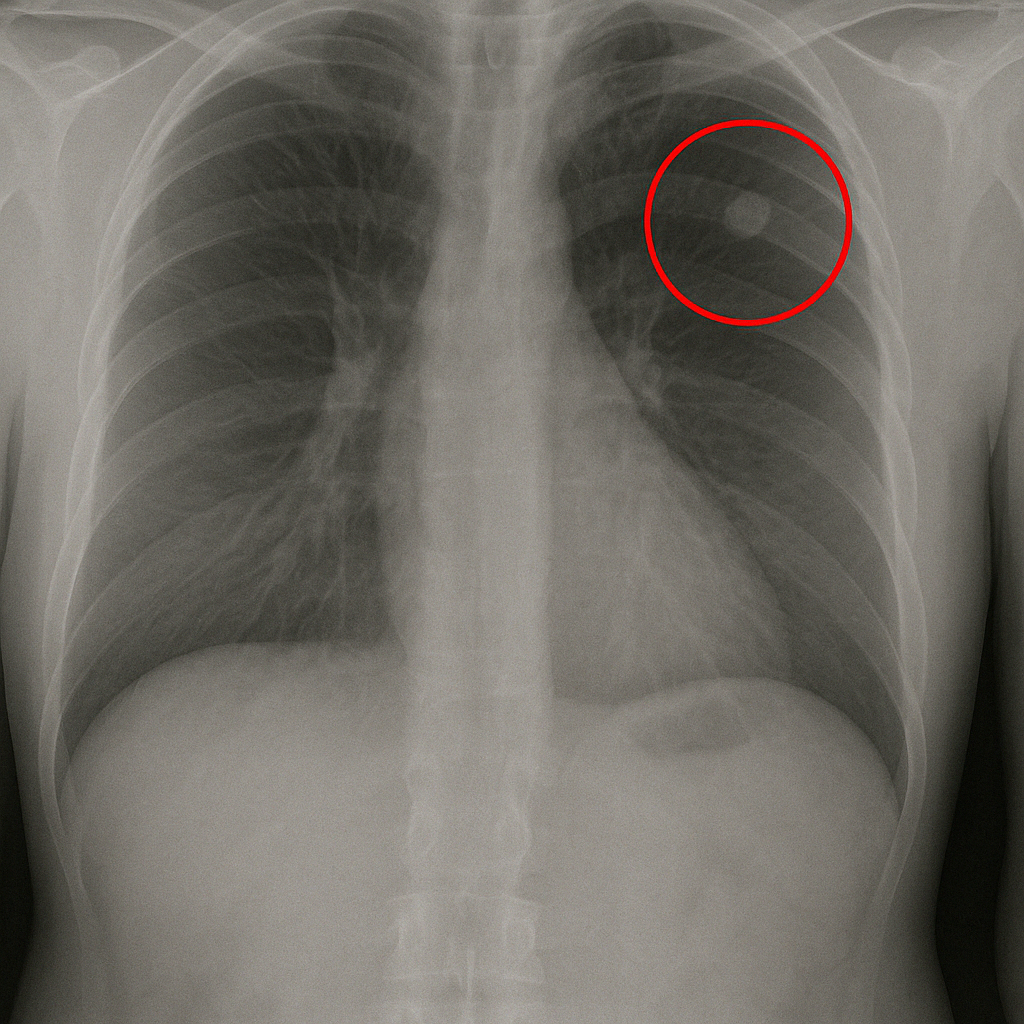

Lung nodules are small, round or oval-shaped growths that can show up in your lungs, usually less than 3 centimeters in size. They appear as a spot or shadow on an X-ray or CT scan. These nodules can be from past infections, benign tumors, or in some cases, they can be an early sign of lung cancer.

The most common ways to spot a lung nodule are through chest X-rays or CT scans. A chest X-ray is usually the first step and can show if there’s something unusual in your lungs. However, because X-rays only provide a basic image, CT scans are often used to get a more detailed look. A CT scan takes multiple X-ray images from different angles to create a comprehensive picture of your lungs, allowing doctors to see nodules more clearly and assess them better.

Size, Shape, and Location of Nodules

The size, shape, and location of a nodule help doctors know whether it’s something to worry about. Generally, smaller nodules (less than 6 millimeters) are less likely to be cancerous, while larger ones may require closer monitoring. The shape also matters—nodules with smooth, round edges are typically less concerning than those with irregular or spiculated (spiked) edges.

Where the nodule is located in your lungs can also provide clues. For example, nodules found in the upper lobes of the lungs are often more suspicious than those in the lower lobes. These characteristics alone don’t tell the whole story, which is why your doctor will consider them along with other factors like your age, smoking history, and any symptoms you might have.